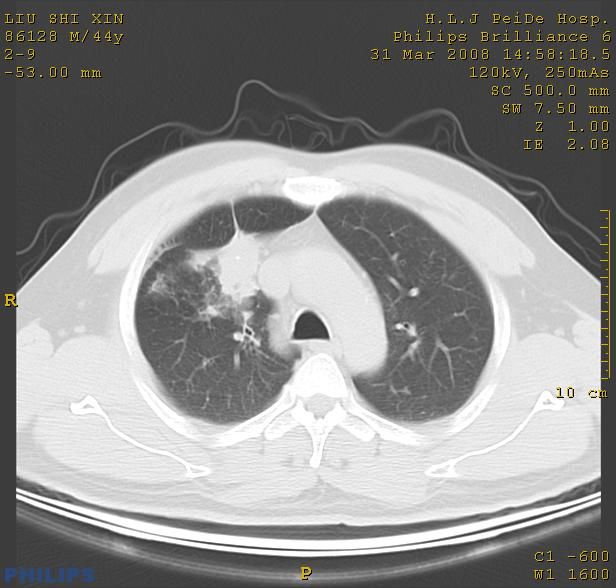

标题: CT13096:请分析胸膜下结节的影像基础是什么 有病理结果 [打印本页]

标题: CT13096:请分析胸膜下结节的影像基础是什么 有病理结果

瘢痕挛缩,胸膜牵拉,血管纠集扭曲,上叶前段支气管显示欠清,周围散在斑片影,以纵隔旁肺癌可能性大。请穿刺检查。

中心型肺癌并阻塞性肺炎及肺内转移

中心型肺癌并阻塞性肺炎、两肺及胸膜多发转移。

结节灶与血管末梢相通象转移灶;小三角状尖部有纤维索是胸膜拉扯征;纵隔旁大片实性影有点状钙化;周围有名显纤维瘢痕征可考虑瘢痕癌

典型的肺癌胸膜转移!没啥鉴别诊断!

本病例有病理结果是,鳞状上皮癌,胸膜下结节影病现诊断的肿大淋巴结,谢谢大家分析,请问胸膜下结节是肿大淋巴结怎么解释